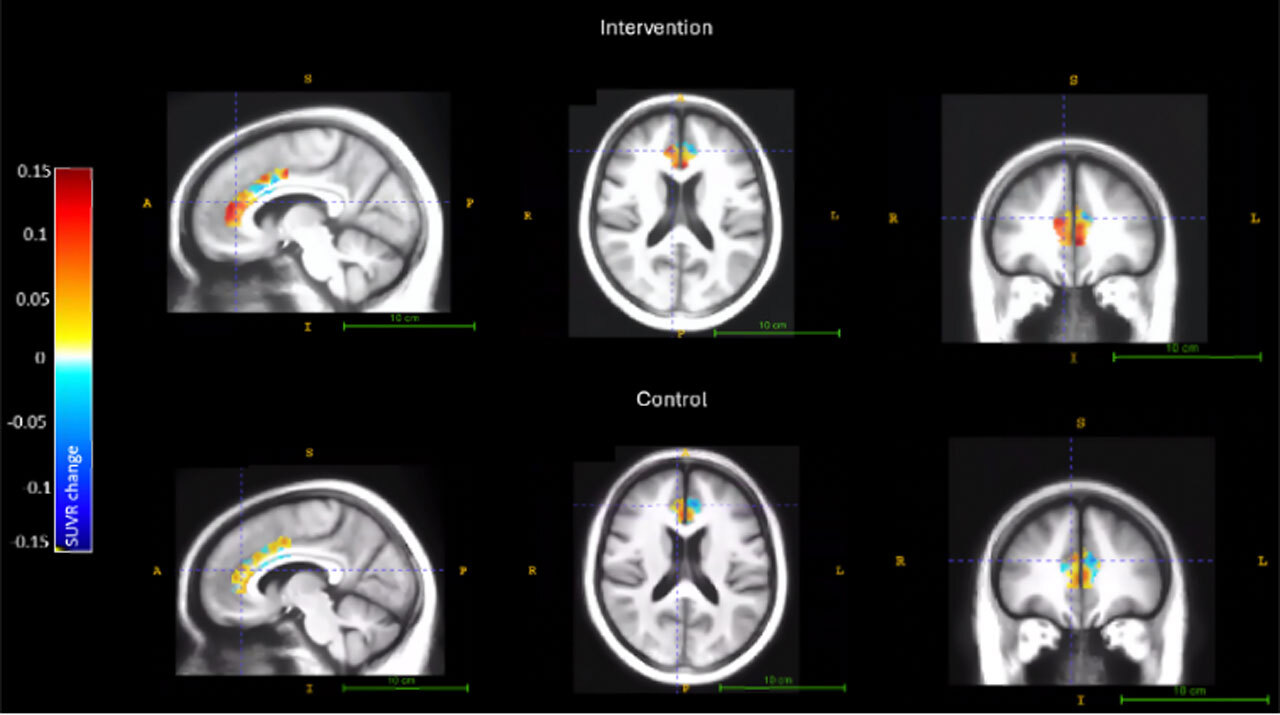

Чтобы отследить изменения в мозге, исследователи использовали специальное ПЭТ-сканирование и трассирующее вещество, которое делает холинергические резервы видимыми на снимках, позволяя увидеть, насколько активна была холинергическая система до и после тренировок.

На позитронно-электронной томографии только участники когнитивных тренировок BrainHQ показали улучшения в холинергической активности: в передней поясной коре — основной области интереса, а также в областях, связанных с памятью — гиппокампе и парагиппокампальной извилине. Одновременно выросла скорость реакции по тестам, и этот эффект сохранялся спустя три месяца по окончании тренировок.